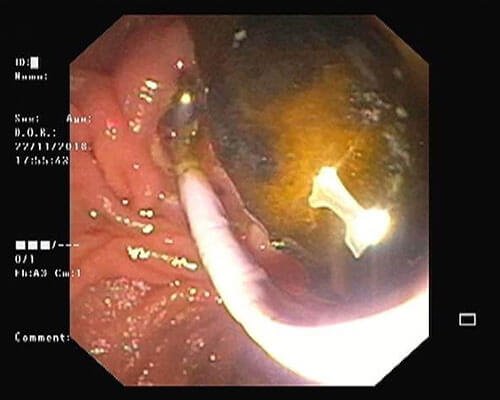

During ERCP stones can be removed form CBD or pancreatic duct and stents can be placed in CBD for treatment of jaundice and in MPD for pain relief

- Removal of worm form CBD or pancreatic duct